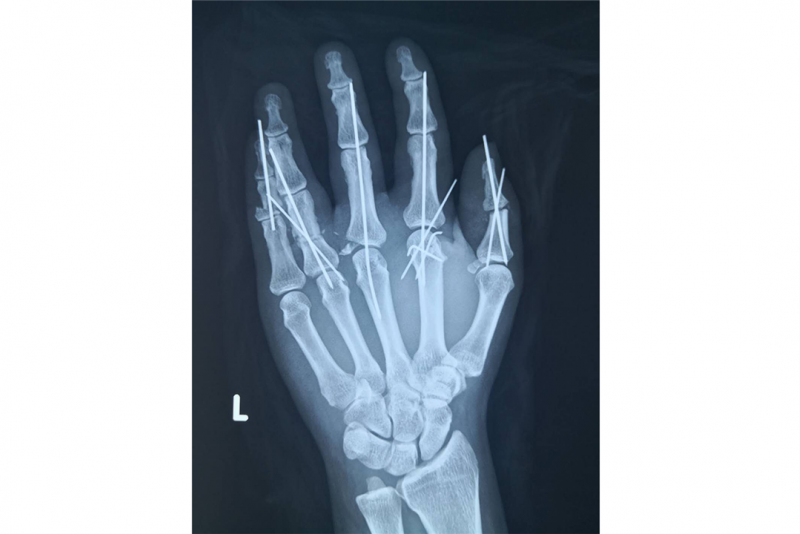

再植术后x线片

经过显微镜下探查发现,患者手指离断平面位于手指根部,血管直径大约0.5-0.8mm,每个手指都需要吻合两根动脉和两根静脉,加上五个手指都需要再植,这就使手术的难度和风险大大增加。